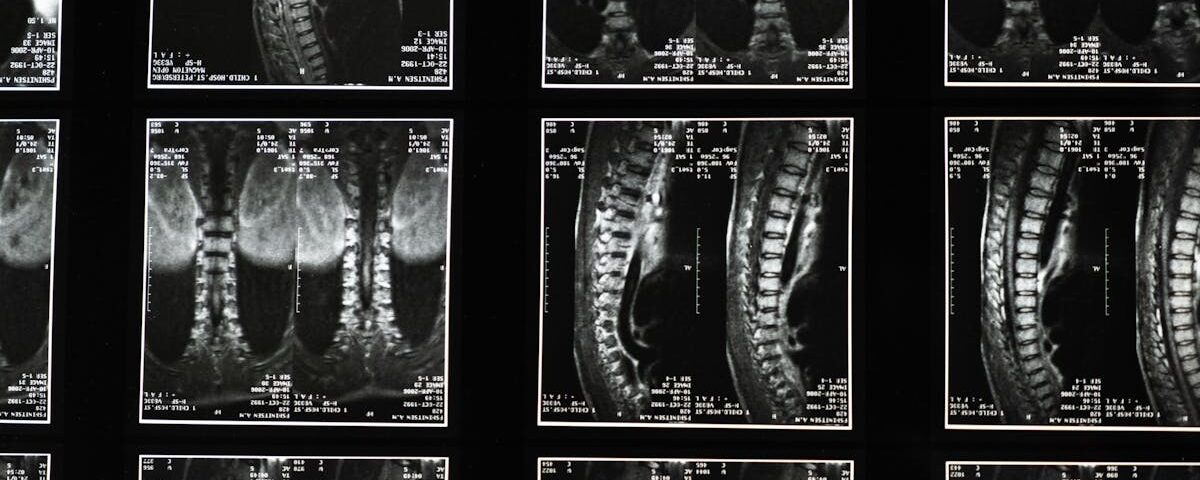

Dans cette catégorie, explorez une méthode innovante et non invasive pour soulager les maux de dos, qu’ils soient aigus ou chroniques. La décompression neurovertébrale cible les disques intervertébraux et les structures nerveuses comprimées, réduisant ainsi la pression, apaisant la douleur et favorisant la régénération des tissus. Nos articles mettent en lumière les bienfaits de cette thérapie de pointe, notamment l’amélioration de la mobilité, la réduction de l’inflammation et la prévention des complications à long terme. Basée sur des données scientifiques, cette approche offre une solution efficace et durable, intégrée dans une stratégie globale de gestion des douleurs dorsales pour améliorer la qualité de vie.